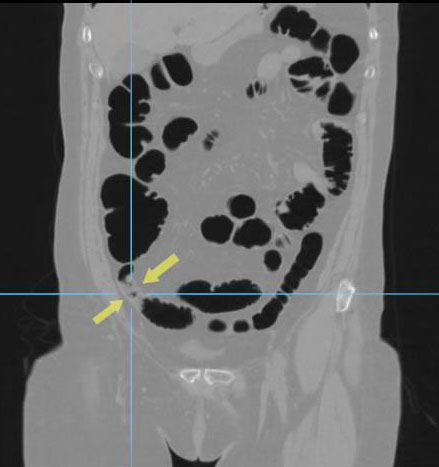

Циркулярный рак тонкой (подвздошной кишки)

Необходимо отметить, что данная патология довольно редко встречается, как правило выявляется на операционном столе у пациентов с тонкокишечной непроходимостью. На данном примере демонстрируем, что дефект кишки был диагностирован на основании 3D реконструкции, а затем уже целенаправленно подтвержден сканограммами с протяженностью процесса и степенью сужения кишечной трубки. Сыграла свою роль сопутствующая патология, которая имела место быть, а именно слабость Баугиниевой заслонки, за счёт чего тонкий кишечник полностью заполнился газом, хотя целью исследования было исключить патологию толстого кишечника.

Просвет тонкой кишки до и после дефекта в 3D-эндоскопе